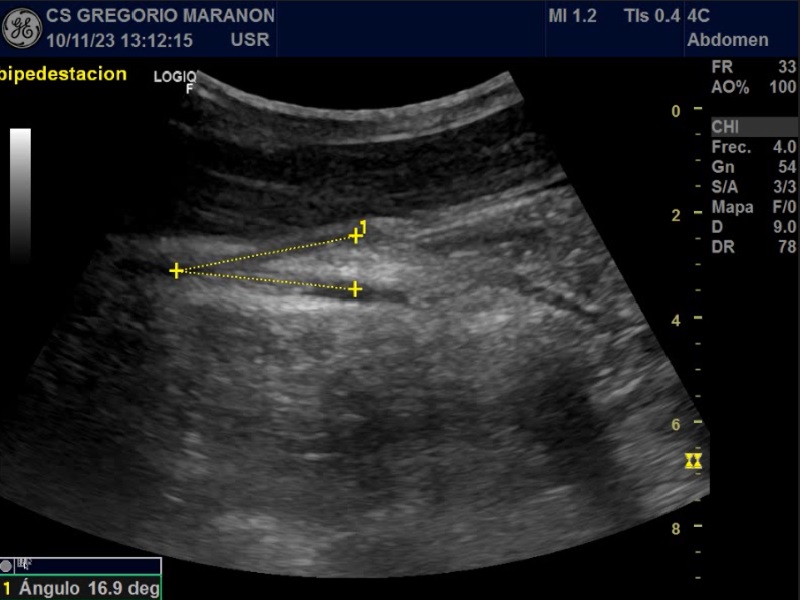

Ecografía clínica donde en el plano transversal vemos una distancia entre Arteria mesentérica superior (AMS) y Aorta de 3 mm y un ángulo entre ellas de 14,3º.

Fisiológicamente, el ángulo formado entre la AMS y la Aorta oscila entre 38 y 65º con una distancia entre ambas de 10 a 28 mm. Cuando estas medidas son menores de 25º o de 8 mm respectivamente, se produce una compresión de la tercera porción del duodeno.

El diagnóstico de esta entidad suele retrasarse debido a su inicio insidioso. La ecografía es un método muy sensible para el diagnóstico del SAMS con una alta correlación con la tomografía axial.